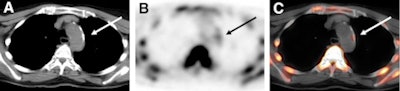

| Transaxial F-18 NaF images from a 76-year-old woman include CT (A), PET (B), and fused PET/CT (C) images of the aortic arch. F-18 NaF uptake in atherosclerotic lesion coincided with calcification, as indicated by the arrows. Images courtesy of the Journal of Nuclear Medicine. |

For the remaining 223 lesions with F-18 NaF uptake (88%), researchers found radiotracer accumulation and calcification. However, the study stated, "only these 223 (12%) of the 1,930 total calcification sites showed prominent 18F-sodium fluoride uptake in at least some part of the calcified plaque."